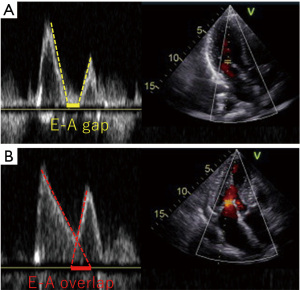

LV diastolic filling consists of early rapid filling (E wave), diastasis, and late atrial contraction (A wave). As HR increases, total diastolic filling time shortens. Because the durations of the E and A waves are relatively preserved, diastasis becomes disproportionately abbreviated, leading to overlap between the E and A waves (E-A overlap) on transmitral Doppler flow (Figure 4) (73,74). Greater E-A overlap has been associated with increased A-wave amplitude and elevated left atrial pressure in both experimental models (75) and human studies (76). These observations suggest that tachycardia-induced E-A overlap reflects impaired diastolic filling and may contribute to elevated filling pressures and pulmonary congestion.

Although modest increases in HR may augment cardiac output, excessive HR elevation can paradoxically worsen hemodynamics by inducing E-A overlap, a phenomenon reflecting incomplete ventricular relaxation. Conversely, excessively low HR may also be hemodynamically unfavorable and can precipitate symptomatic HF, a condition that often necessitates pacemaker implantation. Thus, both tachycardia and excessive bradycardia may represent suboptimal extremes (Figure 5). From this perspective, an individualized HR that minimizes or eliminates E-A overlap may represent a physiologically favorable range rather than a universally applicable target. Because LV systolic and diastolic properties vary among patients, the HR at which E-A overlap disappears is also likely to differ between individuals. Kusunose et al. reported that the presence of E-A overlap was associated with a higher risk of HF readmission and cardiovascular death, and that incorporation of E-A overlap into risk models significantly improved prognostic performance (76).